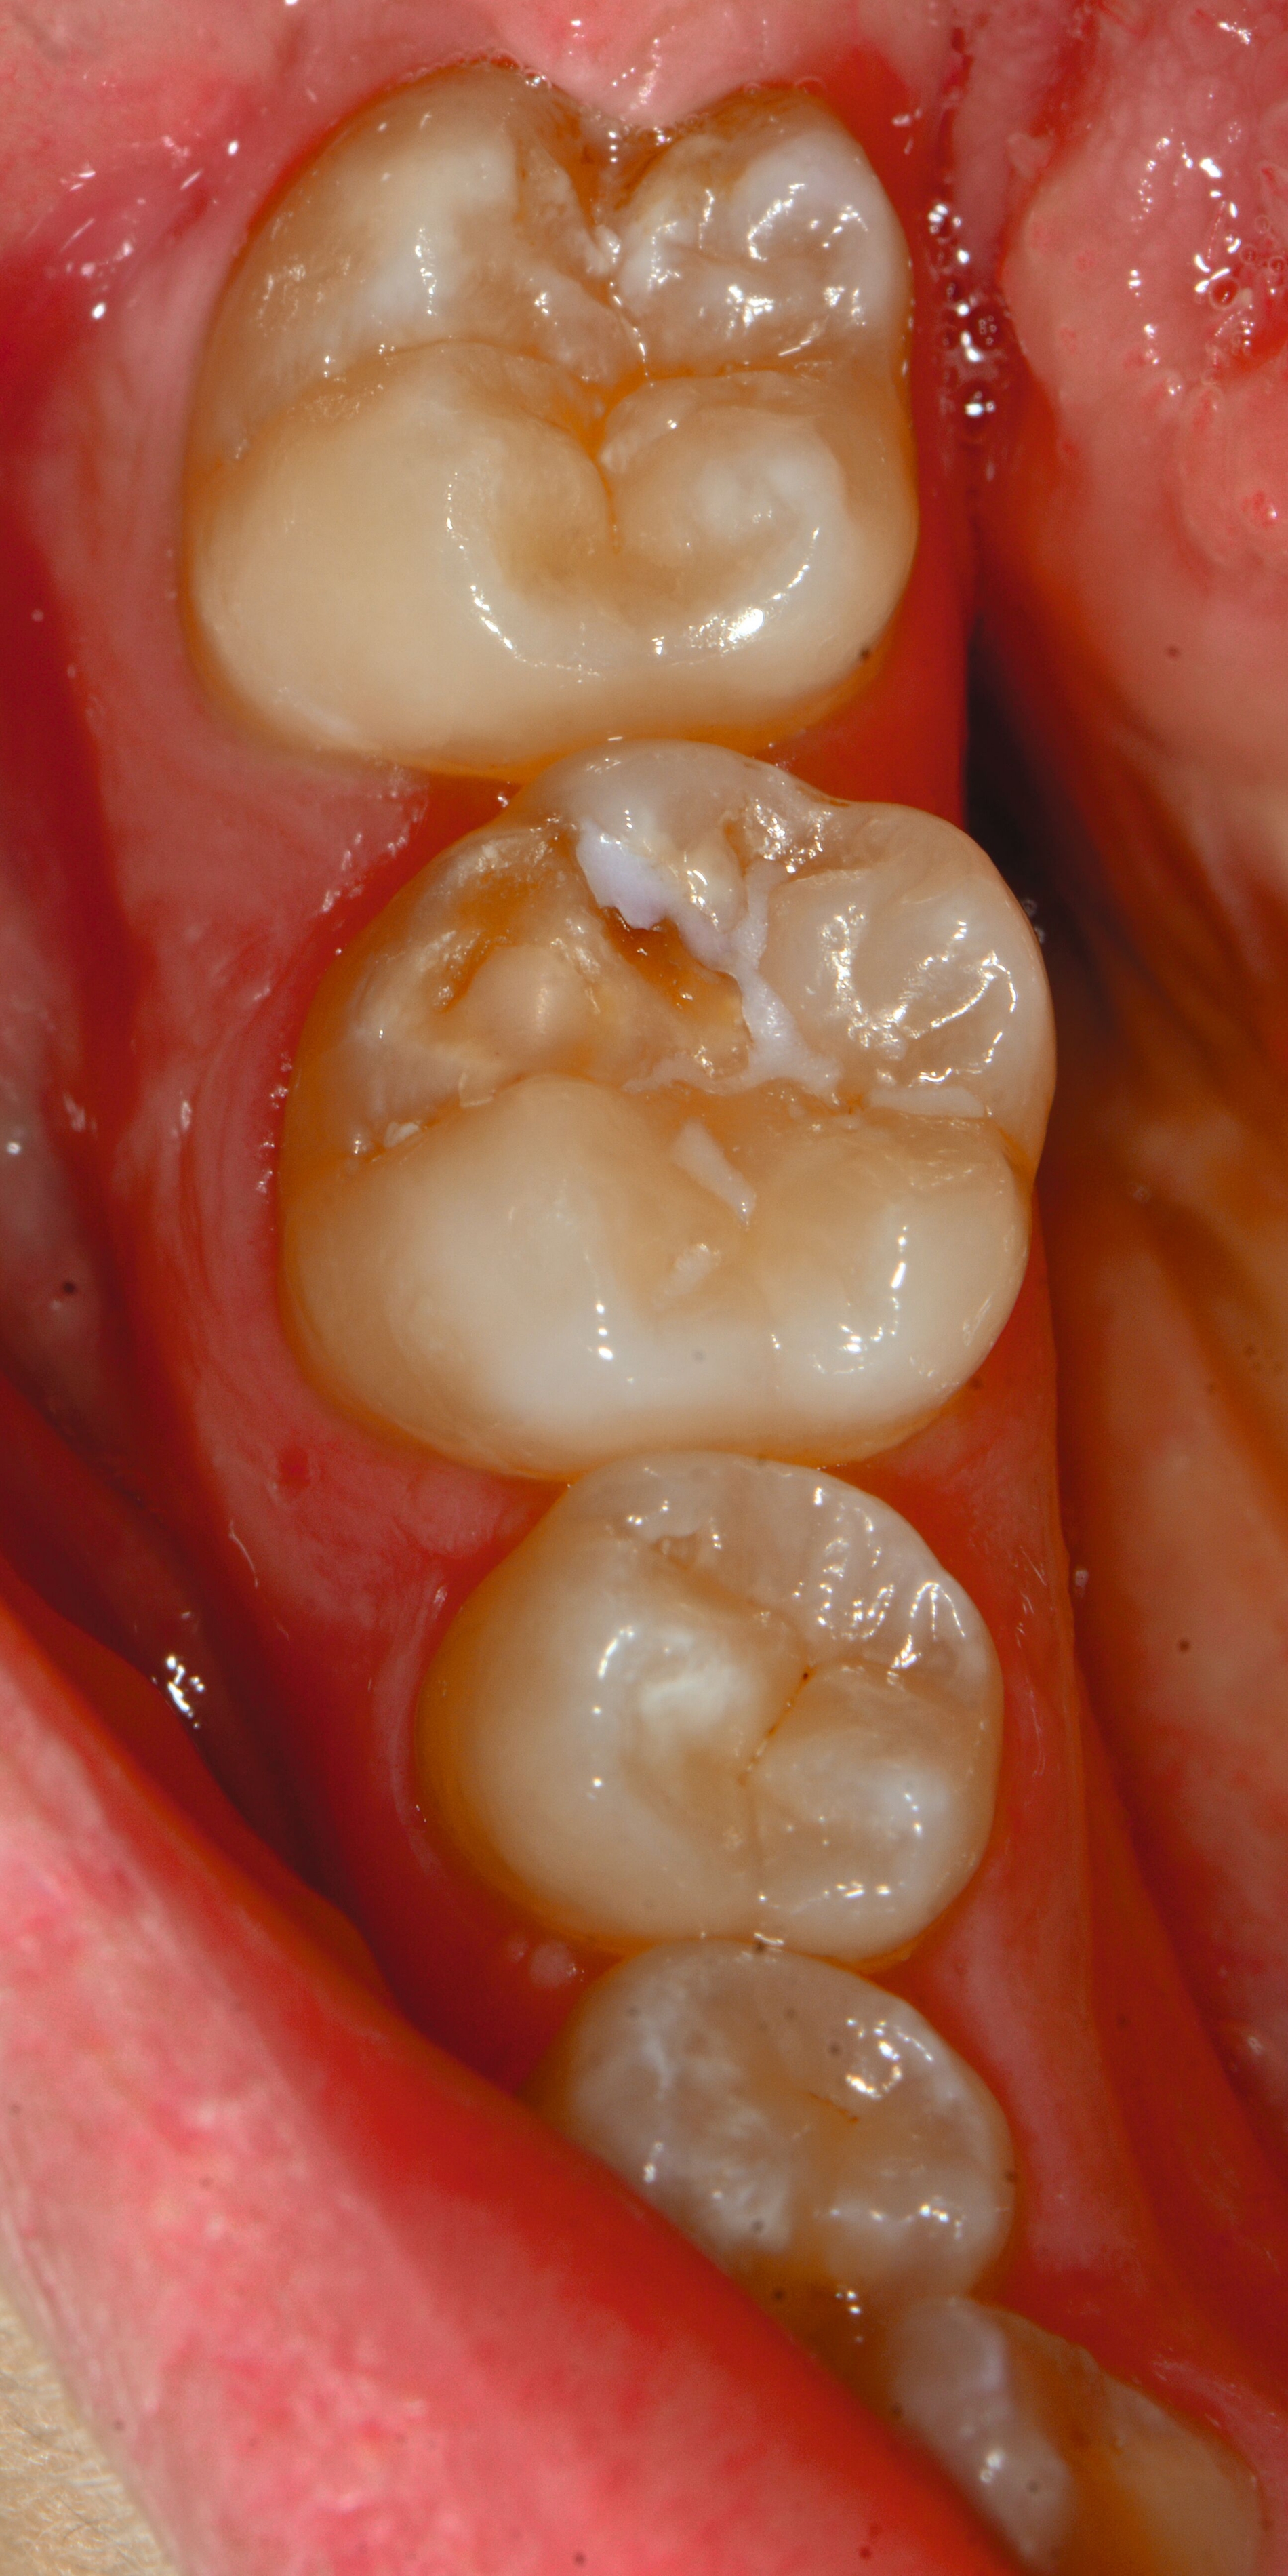

An umfangreich hypomineralisierten Zähnen können Schmelzeinbrüche (engl.: „enamel breakdown“ oder „enamel desintegration“, Abbildung 5) auftreten [Lygidakis et al., 2010; 2022]. Da diese oftmals die Folge einer fehlenden Belastungsfähigkeit des Zahnschmelzes sind und erst nach der Einstellung der Zähne in die Okklusion auftreten, werden sie auch als posteruptive Schmelzeinbrüche bezeichnet. Sie sind häufig im Bereich der Kauflächen beziehungsweise Höcker der Molaren zu finden, führen zur Dentinexposition und damit einhergehend zu ausgeprägten Hypersensitiven insbesondere bei Kindern, deren Zähne gerade erst durchgebrochen sind [Linner et al., 2021].

Frontzähne sind seltener von MIH-bedingten Schmelzeinbrüchen und Hypersensitivitäten betroffen. Von den posteruptiven Oberflächeneinbrüchen sind präeruptive Defekte abzugrenzen. Diese Zähne brechen bereits mit einem vorhandenen Oberflächendefekt in die Mundhöhle durch.

Für die Dokumentation und Klassifikation der MIH wurden verschiedene Systeme vorgeschlagen. Als historisch und veraltet gilt der (modifizierte) DDE-Index. Demgegenüber haben die Kriterien der EAPD – abgegrenzte Opazitäten (Abbildung 3 und 4), Schmelzeinbrüche (Abbildung 5), atypische Restaurationen (Abbildung 6) – mittlerweile die weiteste Verbreitung gefunden. Diese wurden 2003 erstmals zur Beschreibung der MIH auf empirischer Basis publiziert [Weerheijm et al., 2003] und den Jahren 2010 und 2022 im Rahmen der damaligen MIH-Workshops bestätigt [Lygidakis et al., 2010; 2022].